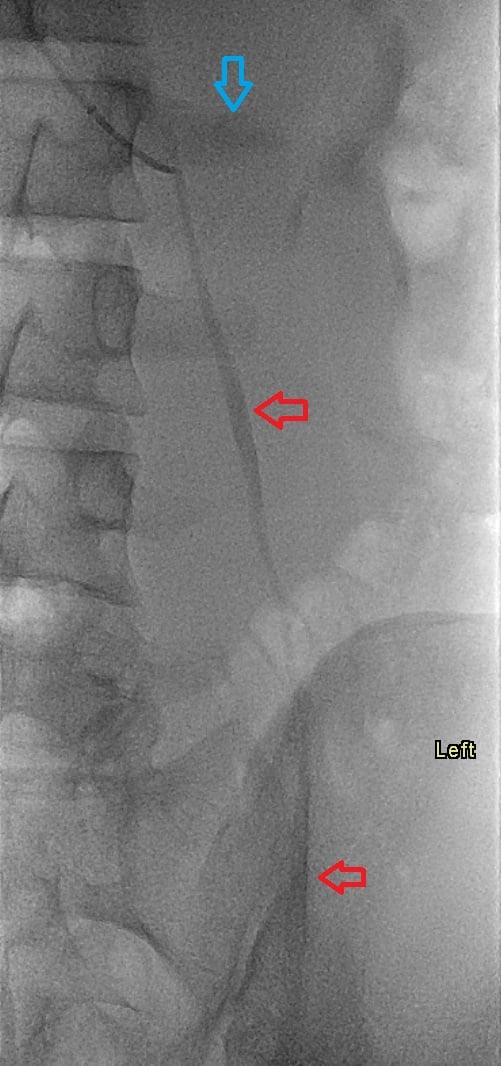

17-year-old male with a long history of left-sided varicoceles status post surgical ligation in 2015 presents with recurrence of symptoms, referred to us for left gonadal vein embolization.

Ultrasound demonstrates enlarged veins (>3 mm) adjacent to the testicle. Angiogram demonstrates reflux of contrast into the left gonadal vein to the level of the scrotum, indicating venous valvular incompetence. Coil embolization and sotradecol sclerotherapy of the left gonadal vein were performed, with an Amplatzer plug at the top of the vein. Repeat angiogram demonstrates no contrast opacification of the vein. Red arrows indicate the left gonadal vein and the blue arrows indicate the left renal vein.